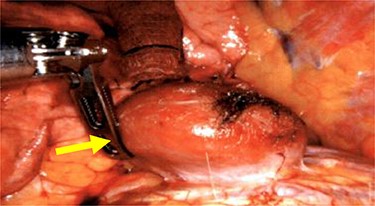

We performed a robotic thoracoscopy with plan for wedge resection and possible completion lobectomy. Gross inspection of the thoracic cavity revealed an abnormal mass on the dome of the diaphragm with the appearance similar to liver (Figs 5 and 6). The mass was noted to be positioned in the oblique fissure and correlated with the location of the larger nodule seen on CT scan. There was a second area of thinned-out diaphragm where a small nodule was noted to be protruding under the diaphragm. This second mass also had the appearance of liver and was consistent with location of smaller lesion on CT scan. A core needle biopsy was performed which was consistent with benign liver tissue. The decision was made not to proceed with any diaphragmatic repair or reinforcement with mesh. This was diagnosed as an asymptomatic herniation through the diaphragm, and the liver was fused to the diaphragm therefore preventing future intestinal herniation.

Liver herniation corresponding to the location of larger lung nodule seen on CT scan.